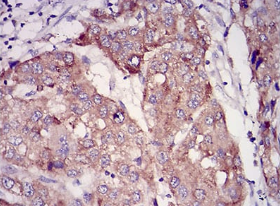

IHC    1/200 - 1/1000